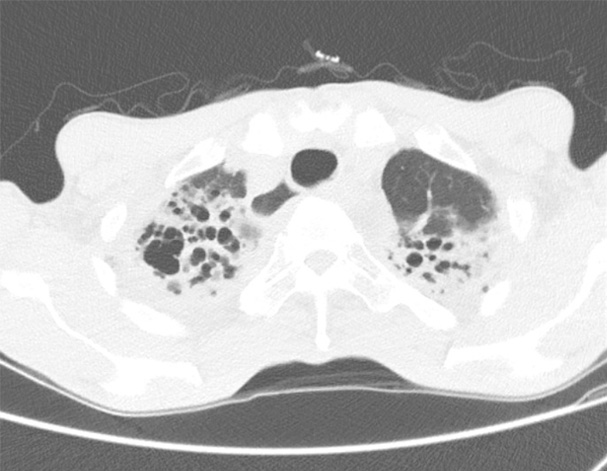

기관지확장증의 CT 사진

비결핵항산균에 감염된 폐사진